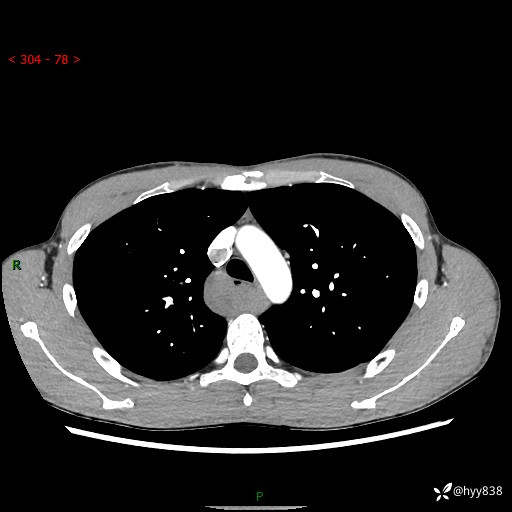

年轻男性,发现后纵隔占位1周余。征象简单,难在定位---结果公布~

现病史:患者于1周前体检行检查发现后纵隔占位,患者平素无明显咳嗽咳痰,无心慌、胸闷、胸痛、呼吸困难、低热、盗汗,无头痛、头晕,无腹痛、腹胀等不适。现患者欲求进一步治疗,遂来我院就诊,以“纵隔占位”收入我科。 患者自起病以来,精神可,睡眠可,饮食可,大小便正常,体重无明显改变。

胸部CT平扫+增强